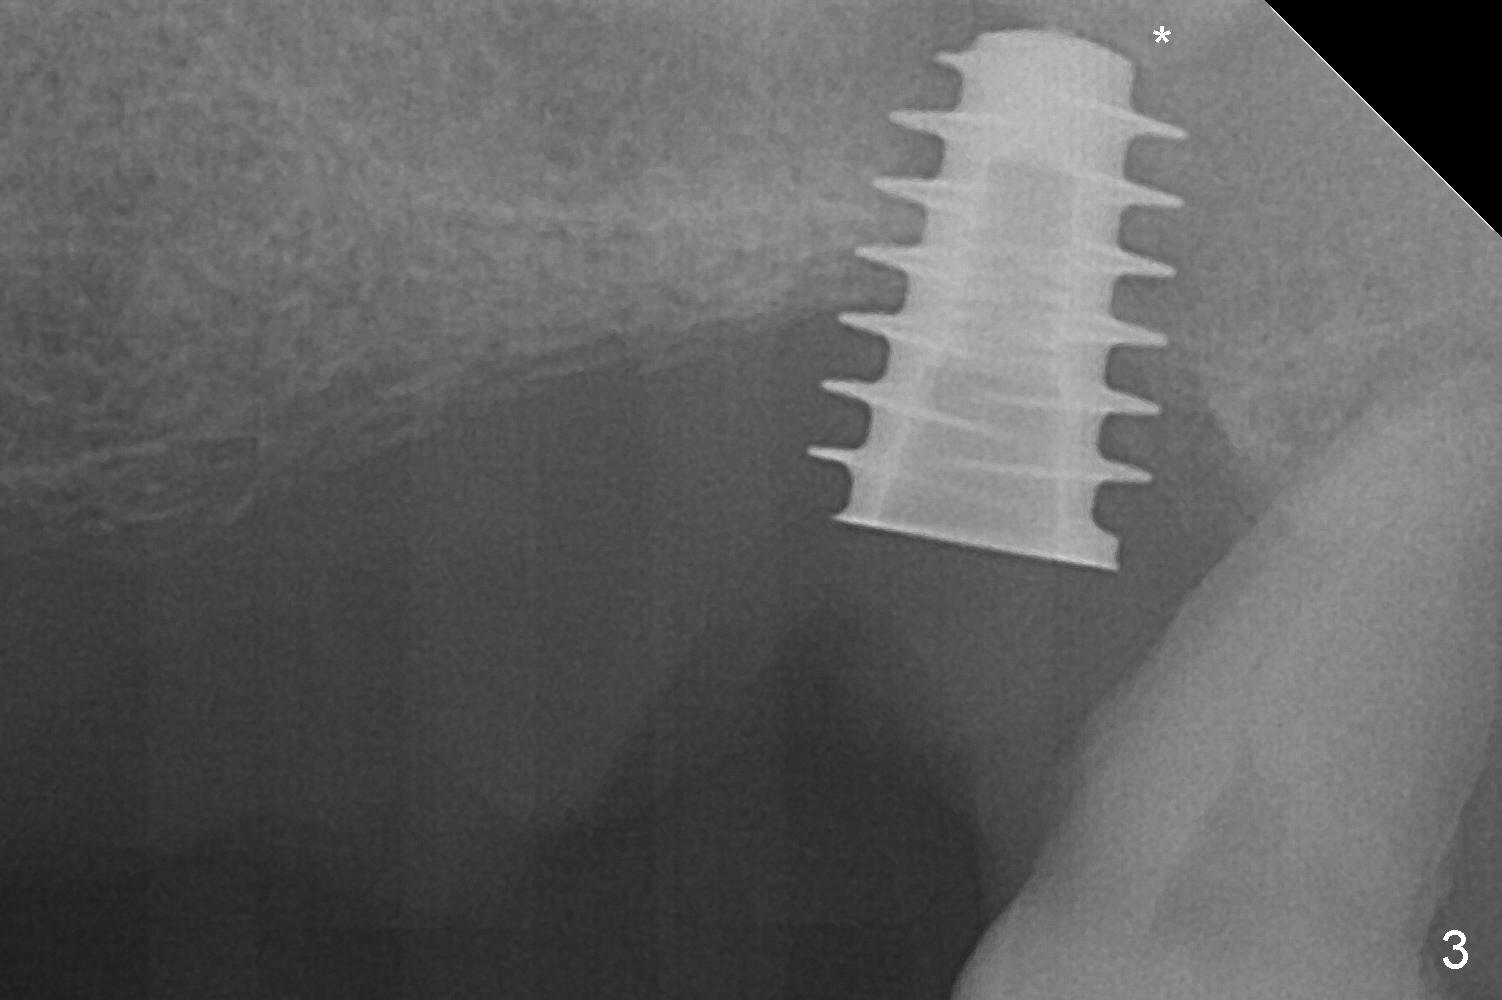

The posterior abutment of the 5-unit FPD, #15 is loose with the buccal roots extruded outside the sockets. The palatal socket is the appropriate site of immediate implant with the presence of the buccomesio-palatal walls, although short. The thinnest portion of the palatal socket is 1.6 mm (Fig.6 CBCT coronal section through the palatal root (P)). Magic Sinus Lifter cannot break through the sinus floor. UF drills are used to create osteotomy and sinus lift until 4.3 mm. A 5 mm tap drill is inserted without stability (Fig.1). A 5.5x9 mm IBS dummy implant achieves insertion torque of 10 Ncm, although it looks smaller (Fig.2) than the tap in Fig.1. After placement of PRF membrane and bone graft (allograft, autogenous bone and Osteogen, Fig.3 *), a 6x9 mm IBS implant is placed with insertion torque of 30 Ncm. It appears that the fins of the implant slice into the bone at high magnification for engagement. Following further placement of the implant, bone graft is packed into the distal portion of the socket (Fig.4 <). The thin fins extends into mesial and distal thicker bone (Fig.5 (CBCT sagittal view) *).